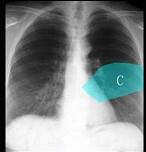

如图所示正常胸部X线影像图像上,该英文字母所代表的肺段为 ( )A.尖段B.后段C.尖后段D.舌叶上段E.前段

问题 如图所示正常胸部X线影像图像上,该英文字母所代表的肺段为 ( )

选项 A.尖段 B.后段 C.尖后段 D.舌叶上段 E.前段

答案 D